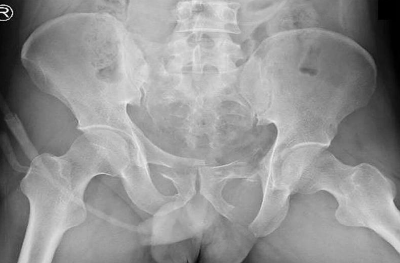

Pelvic ring fracture

X-ray pelvis (AP view)

Bilateral pubic ramus fractures are also present.